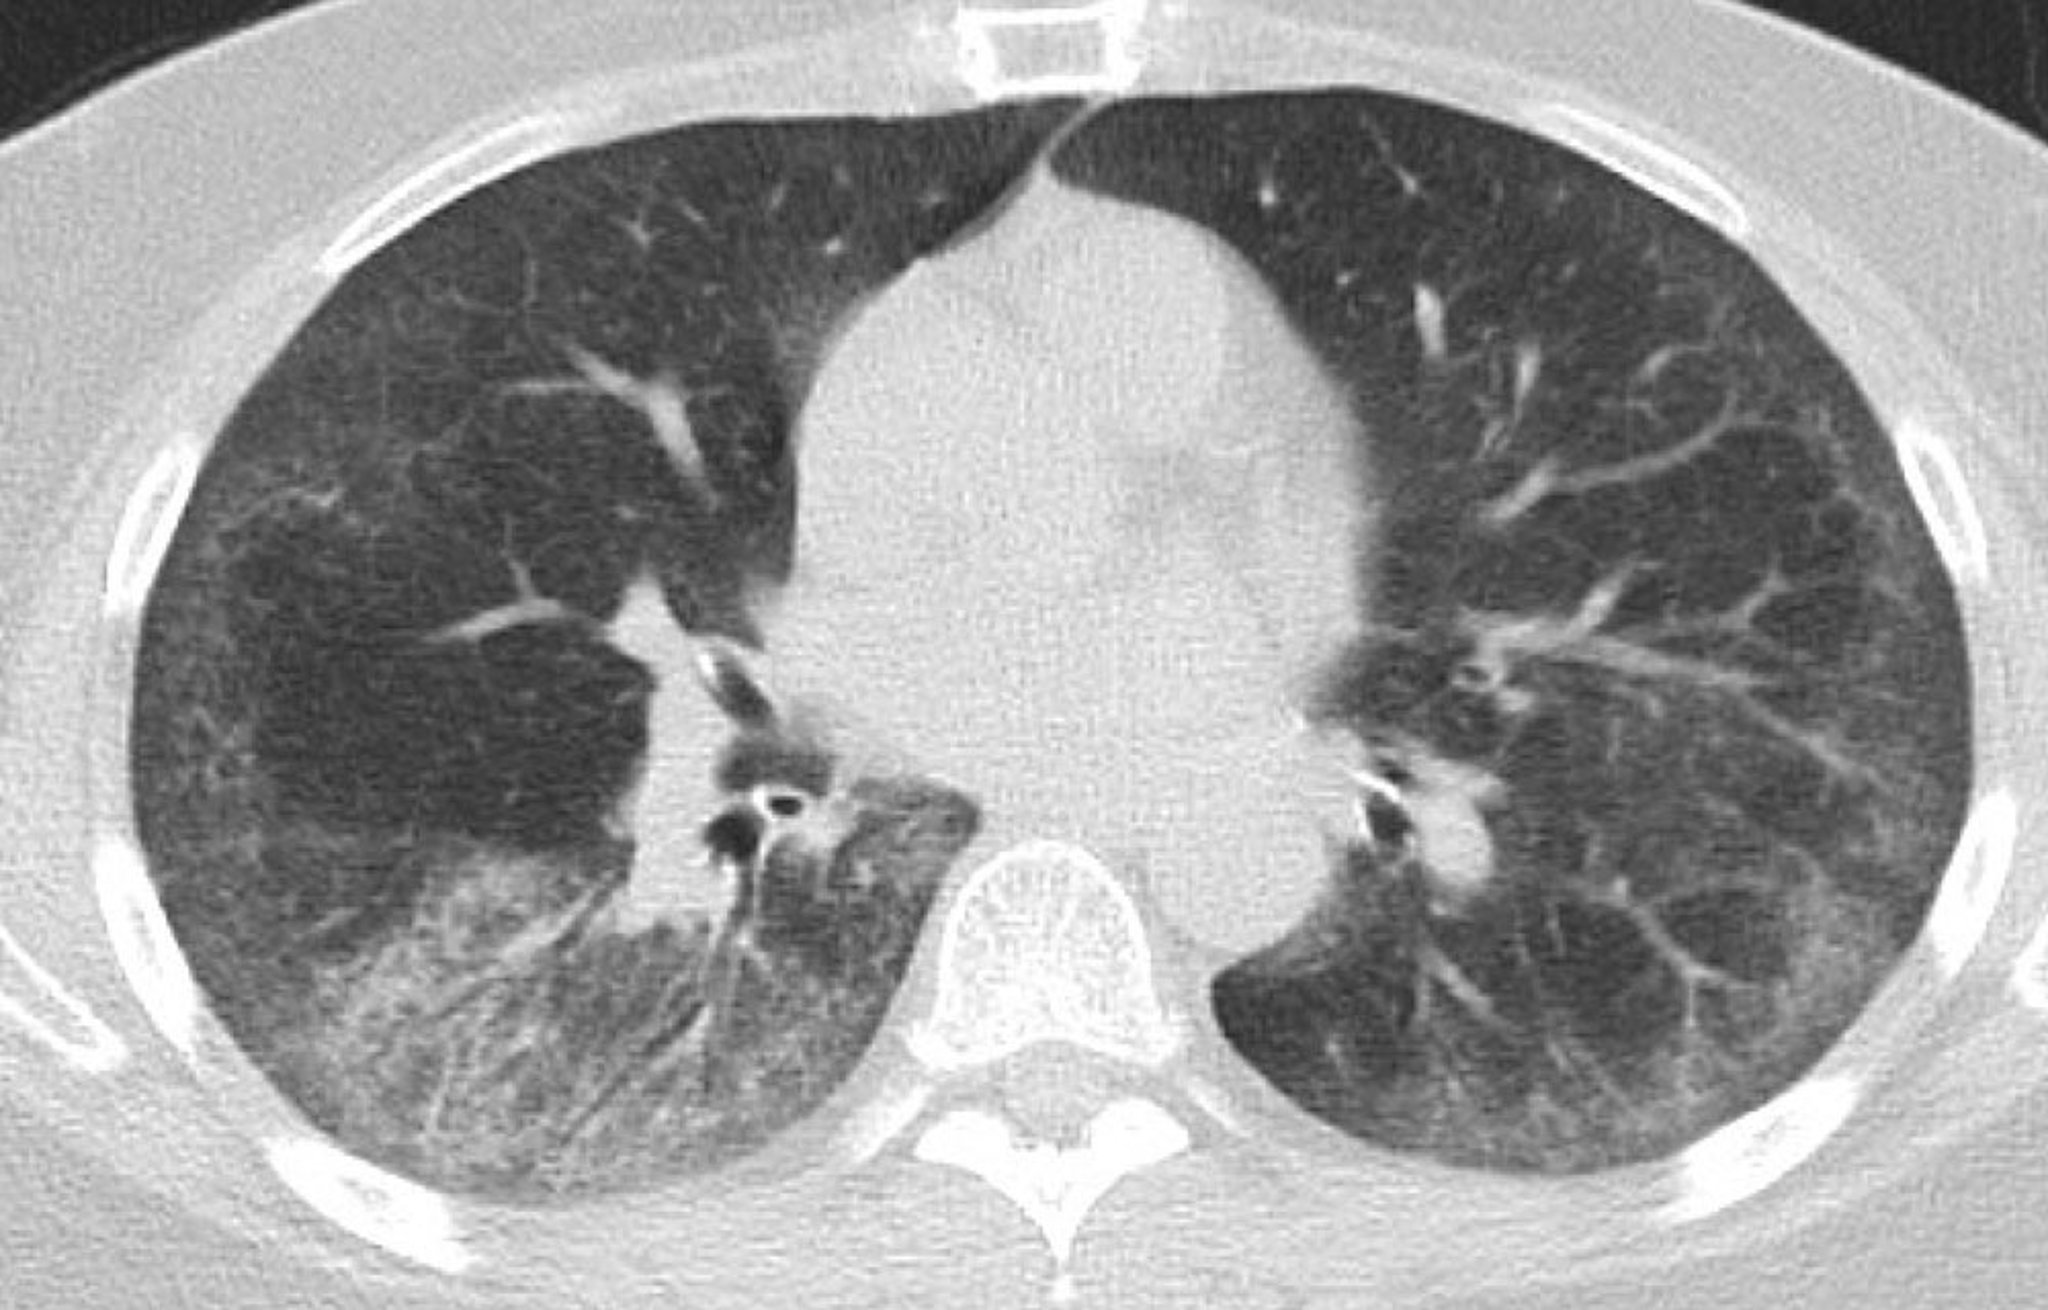

Malattia polmonare interstiziale (TC del torace)

Questa scansione TC mostra opacità bilaterali simmetriche a vetro smerigliato dei lobi inferiori con aree di sottile reticolazione subpleurica; lievi bronchiectasie da trazione in entrambi i polmoni con risparmio subpleurico; e alcuni linfonodi toracici sparsi.

Photo courtesy of Kinanah Yaseen, MD.